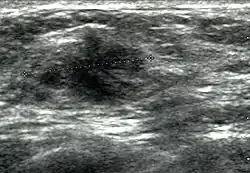

Die diagnostische Differenzierung durch die Sonographie geht heute über die Unterscheidung von zystischen von soliden Befunden hinaus, indem sie die soliden Läsionen in gutartige, wahrscheinlich gutartige, suspekte und hochsuspekte unterscheidet (BIRADS-Klassifikation). Hier sind besonders neben dem internen Echomuster (Echogenität) die Randstrukturen eines Herdbefundes von Relevanz.[11]

Die Mammasonographie wendet heute hochauflösende Breitbandlinearsonden mit einer Frequenz zwischen 2 und 17 MHz an. Zum B-Bild ergänzende technische Entwicklungen zum Zweck der Differenzierung zwischen Gutartigkeit und Bösartigkeit stellen die Farbdopplersonographie zur Darstellung der Blutgefäßversorgung, die 3D-Ultraschall mit ihrer zusätzlichen Aufsichtsebene (C-Ebene) und die Elastographie mit der farblichen Kodierung der Gewebesteifigkeit dar.